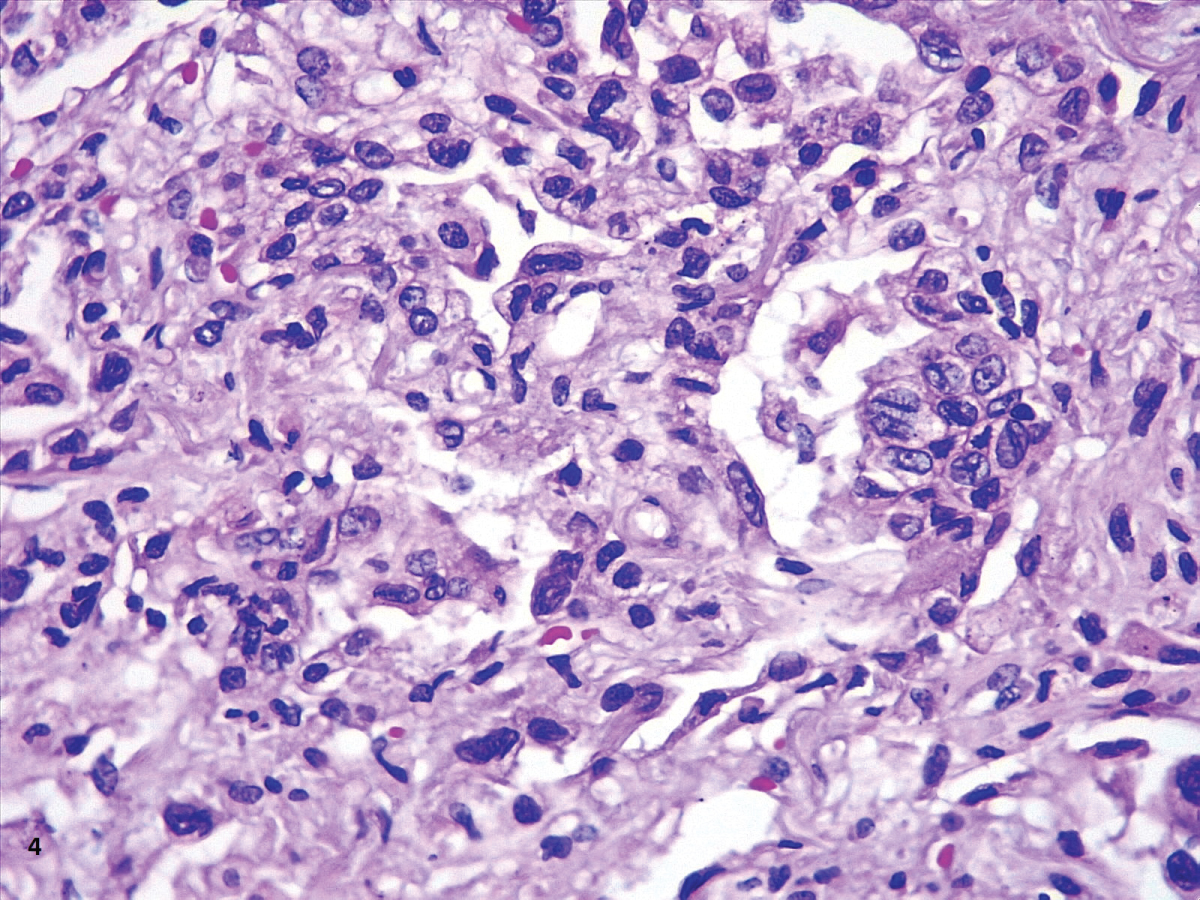

In our cases, we observed markedly congested vessels (Figure 1), and prominent DAD with coexistence of exudative and proliferative phases in most patients (Figure 2 and Figure 3). In the periphery of the more compromised areas, the presence of alveolar microthrombi was striking. The immunohistochemistry with TTF-1 highlighted the hyperplasia of atypical type II pneumocytes (Figure 4); and with CK7 collapsed alveoli were surrounded by a fibroblastic proliferation (Figure 5). As it was observed by others, we found scant inflammatory infiltrates in the majority of cases, but those complicated by bronchopneumonia (Figure 6). We also found giant multinucleated cells, which were positive to CK7, and had cytopathic-like changes in the majority of cases (Figure 7). The cytopathic-like changes consisted of large nuclei, nucleolar inclusions, lumpy chromatin, and a large, eosinophilic cytoplasm; however, these changes are not specific for Sars-cov-2, therefore they cannot be used as diagnostic criteria for COVID-19 pneumonia. Variable amounts of CD68 positive alveolar macrophages were identified (Figure 8). Interestingly, higher amounts of alveolar macrophages were observed in patients with the highest values of ferritin (observation not systematized). This finding correlates with the role of ferritin in macrophage activation and the proposal to include COVID-19 within the hyperferritinemic syndromes [38].

Figure 3: The immunohistochemistry with TTF-1 highlighted the hyperplasia of atypical type II pneumocytes. View Figure 3